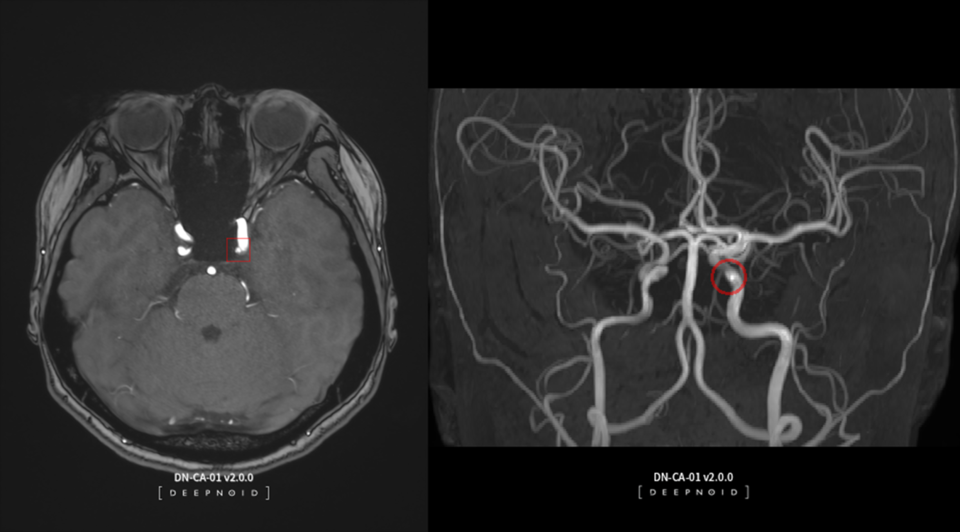

이에 따라 딥뉴로를 도입한 병원은 뇌동맥류가 의심되는 환자에게 비급여 청구할 수 있다. 딥뉴로는 뇌혈관 자가공명혈관조영술(MRA) 영상에서 뇌동맥류 의심 부위를 AI로 판독 및 분석해 의료인의 진단을 보조하는 영상 진단 솔루션이다.